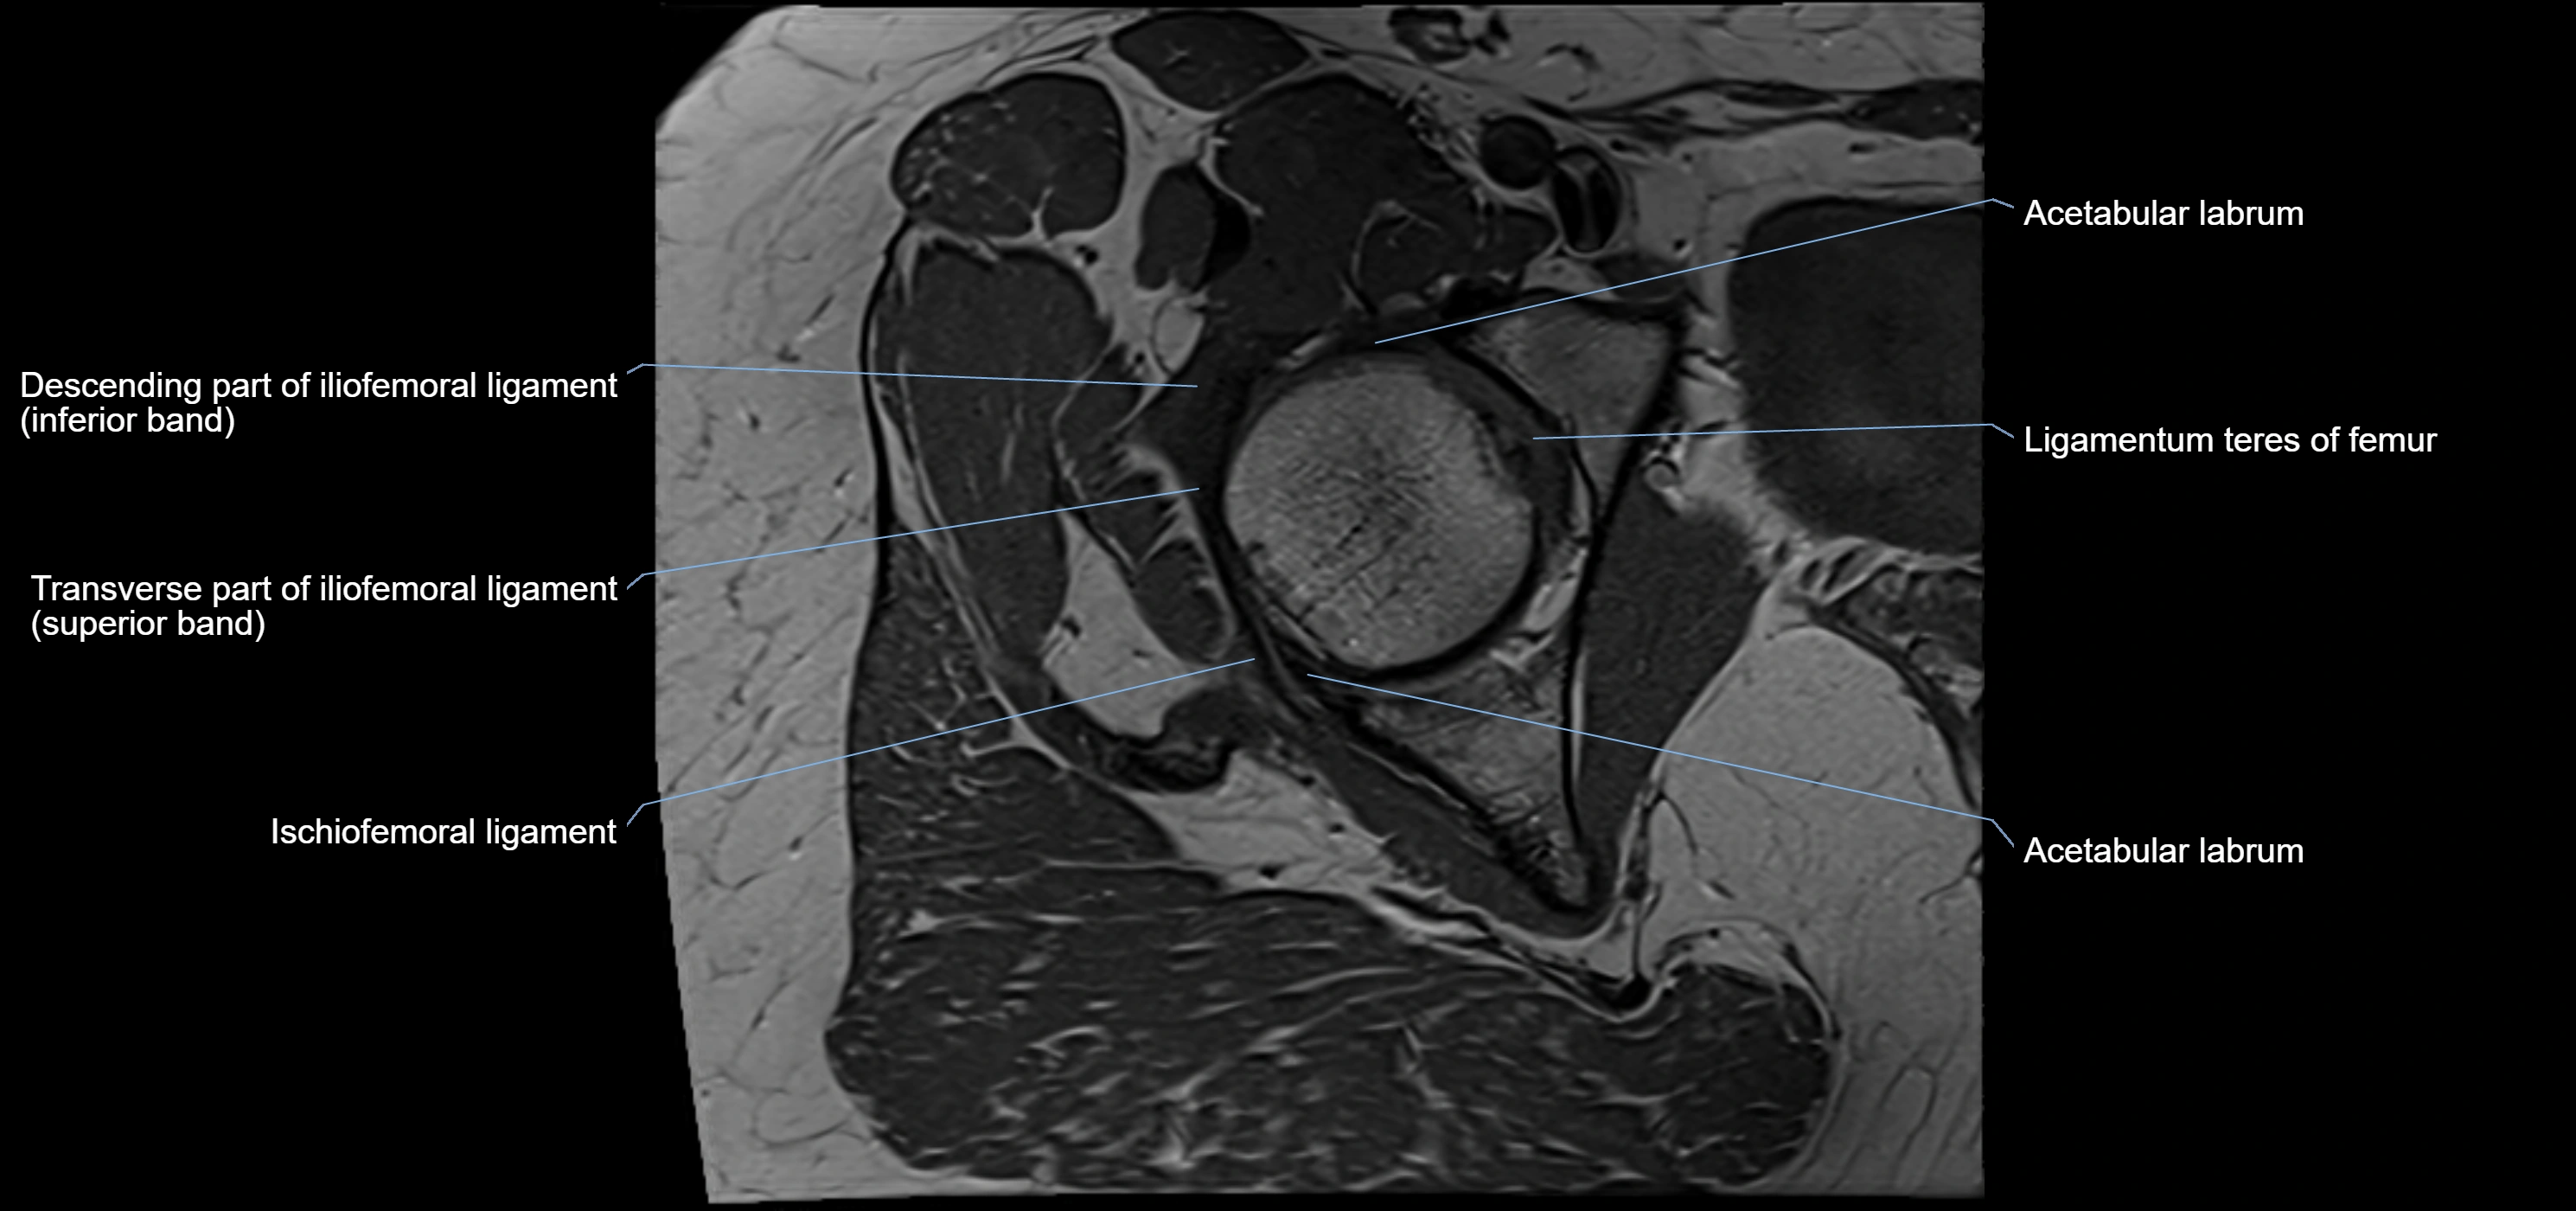

MRI Appearance

T1-weighted images:

• Labrum: low signal intensity (dark)

• Surrounded by intermediate signal joint fluid (bright on arthrogram)

• Tears: linear or focal areas of intermediate-to-high signal interrupting labral continuity

T2-weighted images:

• Joint fluid: bright, making labral tears visible as fluid extending into or around labrum

• Degeneration: may show areas of increased signal within labrum

MRI image

image